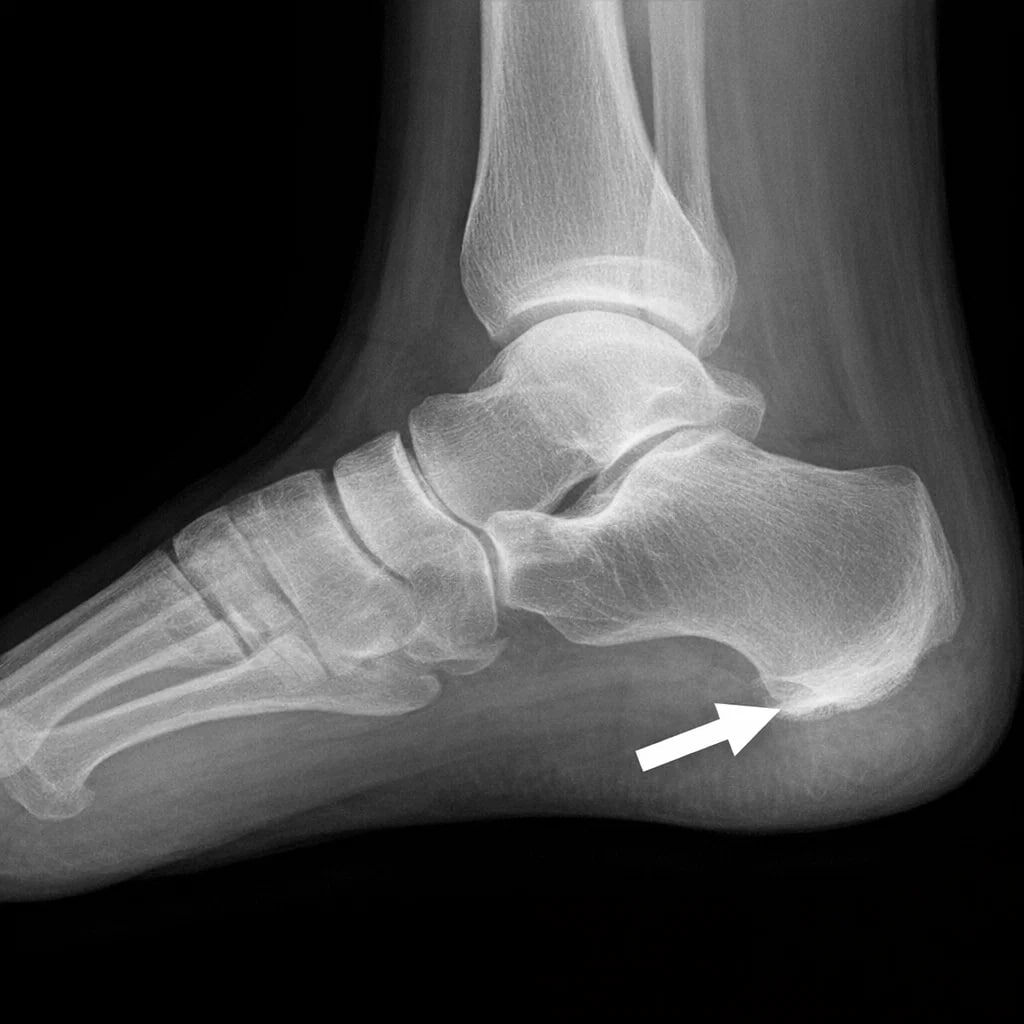

ИЗ-ЗА ЧЕГО ПОЯВЛЯЕТСЯ ПЯТОЧНАЯ ШПОРА 🦶

Так со временем формируется шпора